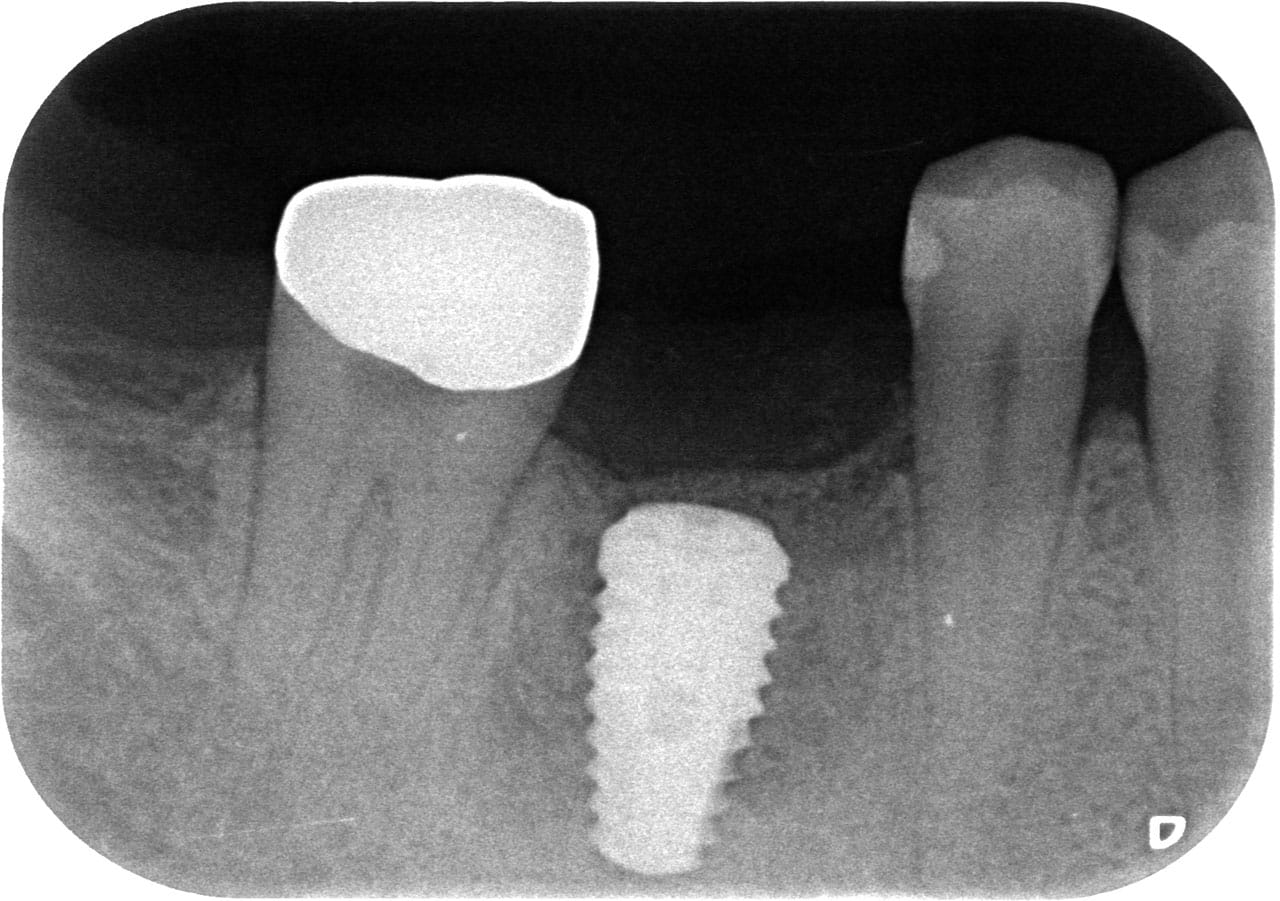

3D(CB)CTデータには、従来の2Dレントゲン写真よりも多くの情報が含まれています。

この豊富な情報をもとに製作したインプラントポジションのプランニングとサージカルガイドが、外科手術の信頼感と安心感を高めます。

またガイデッドサージェリーによって低侵襲手術が可能となり、患者様の負担の軽減が期待できます。